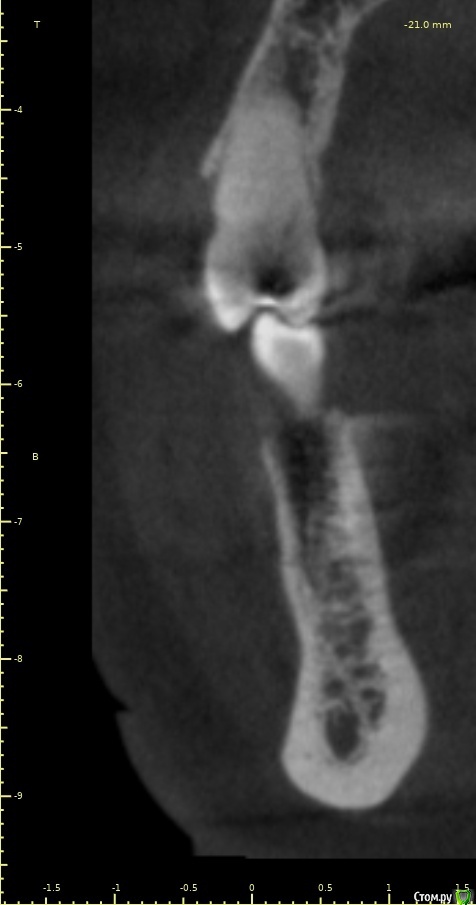

Женька Опубликовано 28 ноября, 2020 Поделиться Опубликовано 28 ноября, 2020 (изменено) Приветствую коллеги. В общем три недели назад 07.11.20 установил пациентке 2 имплантата в позиции 45-46. Гребень по ширине был около 6.5мм в области 4.5 и около 7.2мм в области 4.6 (с учётом заглубления на 1.5-2мм). Это была наверное первая имплантация во время которой я чувствовал себя спокойно и расслабленно. Всё прошло хорошо, немного покопался с непосредственным введением имплантатов, тк никак не хотели топиться на нужные 1.5мм. Поэтому пробовал методику с выкручиванием на пару витков и снова закручиванием. Особого толку не получил, потому взял финальную фрезу и чуть углублял ложе. Так несколько раз, тк боялся всё-таки немного что задену менталис и нлн. Ввиду того, что биотип у пациентки тончайший и язычно было совсем-совсем тонко - заглушки и швы. Назначил нпвс, ванны хг, аб терапию. Но на утро следующего дня пациентка сказала, что чувствует себя шикарно, решили что нпвс оставим, а аб терапию применять не будем (и грешу что в этом мою ошибка).Через неделю сняли швы, всё отлично.Спустя два дня после снятия начались какие-то "костные" боли, как говорит пациентка в области 4.5 импланта. Которые то отпускают, то снова наплывают. На 4.4 есть дефект твердых тканей (на фото виден), но судя по всему беспокоит не он .Пальпация вестибулярно в проекции 4.5 импланта болезненна, небольшая гиперемия, отёка нет. Гигиену пациентка запустила, тк боялась туда залезать и чистить. Снимки прилагаю первые два от 07.11, два последующих 28.11. Ну и внутри ротовые день операции и сегодняшние числа.Похоже 4.5 на выход? своими "туда-сюда" наверняка я нагрел всё что можно... снова расстройство в той работе, где накосячить предельно сложно... Добавка: пить аб ведь сейчас уже бесполезно? Изменено 28 ноября, 2020 пользователем Женька Ссылка на комментарий

колесников Опубликовано 28 ноября, 2020 Поделиться Опубликовано 28 ноября, 2020 (изменено) Имплант 13 мм? Зачем? При планировании видно, что он упирается апексом в кортикалку. По этому и поставить не могли сразу. Торк 45. Если имплант плотно контактирует с компактной пластинкой,она резорбируется окончато,со всеми вытекающими. Стоило выбрать имплант 8.5мм. Если притопили имплант,зачем поставили заглушку? Имплант зарастёт придётся выпиливать ,откапывать заглушку,ломать то что наросло непосильным трудом. Хороший торк-ставьте рабочий фдм. Сомнения-мелкий фдм или заглушка +1. Рекомендую сделать контрольный кт и поставить фдм Изменено 28 ноября, 2020 пользователем колесников 5 Ссылка на комментарий

Женька Опубликовано 14 декабря, 2020 Автор Поделиться Опубликовано 14 декабря, 2020 (изменено) Наконец-то получил КТ от пациентки...Боли значительно уменьшились, практически не беспокоит... Коллеги, что думаете? Я так понимаю это уже не фон от титана? и вердикт всё-таки один? Сам склоняюсь всё-таки более к понаблюдать. Вестибулярно конечно очень тонко Толщина была ~ 6.7мм Изменено 14 декабря, 2020 пользователем Женька Ссылка на комментарий

Irouil Опубликовано 14 декабря, 2020 Поделиться Опубликовано 14 декабря, 2020 Ну и где тут язычно передавленная кортикалка? Меня смущает только картина в области верхушки симптомного винта, ну и заглубление Я бы дождался уже срока интеграции Ссылка на комментарий

Женька Опубликовано 14 декабря, 2020 Автор Поделиться Опубликовано 14 декабря, 2020 Ну и где тут язычно передавленная кортикалка? Меня смущает только картина в области верхушки симптомного винта, ну и заглублениеНе знаю, я про язычную кортику не говорил. Меня тоже смущает... и в области соседа такого фона (а это не фон я уверен) нет... А с заглублением что не так? по прицелам там 1.5-2мм, на кт почему-то этих мм вообще нет и как будто крестально стоят Ссылка на комментарий